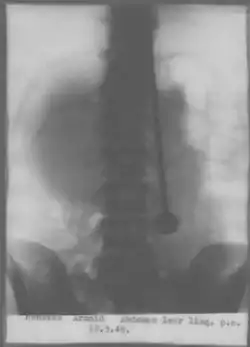

Arnold Gerrit Henskes (6 August 1912 – 26 May 1948), known by the pseudonym Mirin Dajo, was a Dutch performer.[1] He became famous for radically piercing his body with all kinds of objects apparently without injury, even surprising the medical community at the time.[2]

Although not as widely documented as his sword piercing feats, Dajo claimed that his invulnerability had been proven by numerous means. In an interview in Time magazine, he also declared his invulnerability having been tested with burning irons, boiling water, and having been shot through the head from half a yard distance on two occasions. He supported this by exhibiting two scars allegedly from the shots, one in the centre of the forehead and the other above his right eye,[4] however, his autopsy showed no traces of any injuries to the head.[3]

In 1947, Dajo moved to Switzerland and initially was only granted a license to perform without the ability to speak to the public. In his performances Dajo used several assistants but, after many disappointments, he paired up with Jan Dirk de Groot who was his Dutch neighbour. According to De Groot, Dajo had several guardian angels, was telepathic, and could heal people.[2] Time magazine reported on an appearance at the Coors Theatre in Zürich. The article alleged "that Dajo had 'proved' to Zurich doctors that his act was not based on fakery."[4]

On May 11, 1948, Dajo alleged that he was instructed by voices to eat a steel needle. It was surgically removed on May 13, 1948. He would need to spend much time recovering in the hospital, and to demonstrate his health he walked through Zurich directly after being released. Ten days later, when De Groot picked up his wife from the airport, Dajo lay down on a bed and went into a trance-like state. On arrival De Groot's wife was not comfortable with someone lying down as if dead, and asked De Groot to check his health. On the third day De Groot's wife asked him to check again, this time his neck felt cold.[5] The medical examiner announced he had been dead for a day. The autopsy revealed Dajo had died of an aortic rupture.[2]